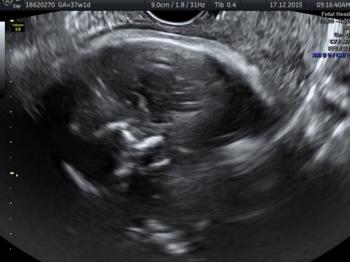

In a third study, ultrasound and fetal MRI were performed on pregnant patients with Zika virus infection at different gestational ages. Once the babies were born, they underwent ultrasound, CT and MRI. The researchers then created 3-D virtual and physical models of the skulls. More than half the babies had microcephaly, brain calcifications and loss of brain tissue volume, along with other structural changes.

"The emergence of Zika virus in the Americas has coincided with increased reports of babies born with microcephaly," said study author Heron Werner Jr., M.D., Ph.D., from the Department of Radiology at Clínica de Diagnóstico por Imagem. "An early diagnosis may help in treating these babies after birth. Moreover, the knowledge of abnormalities present in the central nervous system may give hints about the pathophysiology of the disease."